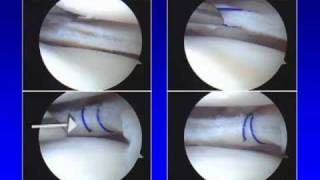

Surgical Techniques

Detailed procedural videos demonstrating Dr. Stone's innovative techniques with embedded Vimeo players and full transcripts.

Knee Procedures

8 videosAnkle Procedures